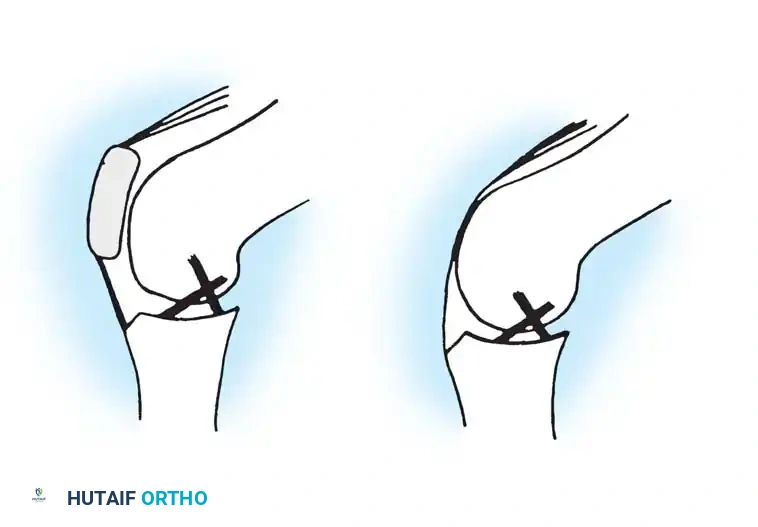

To understand the failure mechanisms in these knees, one must understand the kinematics of the normal knee. Sledge and Ewald elegantly described the knee as a "four-bar linkage system" comprising the quadriceps tendon, the patellar tendon, the anterior cruciate ligament (ACL), and the posterior cruciate ligament (PCL).

The patella acts as a critical fulcrum, increasing the moment arm of the extensor mechanism. Loss of the patella results in a considerable alteration of the mechanical axis and destroys this four-bar linkage. Without the anterior counter-force provided by the intact extensor mechanism, the PCL and posterior capsule are subjected to immense stress and are ultimately incapable of maintaining long-term sagittal plane stability.